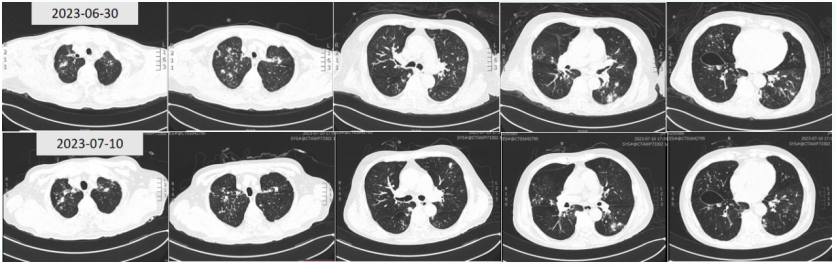

• 胸部CT: 双肺空洞, 结节, 部分伴晕征(图1)

图片

1  患者入院后胸部CT(2023-05-08)

患者入科后予奈玛特韦/利托那韦抗新冠病毒,两性霉素B胆固醇硫酸酯复合物抗真菌,美罗培南抗细菌,同时予无创通气+湿化氧疗,化痰、解痉及对症支持治疗,病情有所好转(图2)

5月16日复查胸部CT:肺部病变明显好转空洞变薄,部分结节消失(图4)

4  复查胸部CT(2023-05-16)

5月25日,患者仍感气促,血气分析(鼻导管吸氧5 L/min)pH 7.29PaCO2 88 mmHgPaO2 53 mmHgSaO2 83 %HCO3- 42.3 mmol/L,再次转入RICU。复查胸部CT:病灶部分较前吸收变小,但空洞内部变实,另有新增空洞及结节(图6)考虑除了基础疾病,感染也未得到很好的控制。

6  复查胸部CT(2023-05-25)

9  复查胸部CT(2023-06-06)

6月20日,待患者情况稳定后复查胸部CT:较6月6日出现新的病变(图12)。再次启动两性霉素B胆固醇酯质复合物(50~100~150 mg/d)抗真菌,同时予头孢哌酮舒巴坦+多黏菌素B(静脉+雾化)抗细菌治疗。

12  患者胸部CT(2023-06-20)

复查胸部CT示病变较前吸收(图16)

16  复查胸部CT